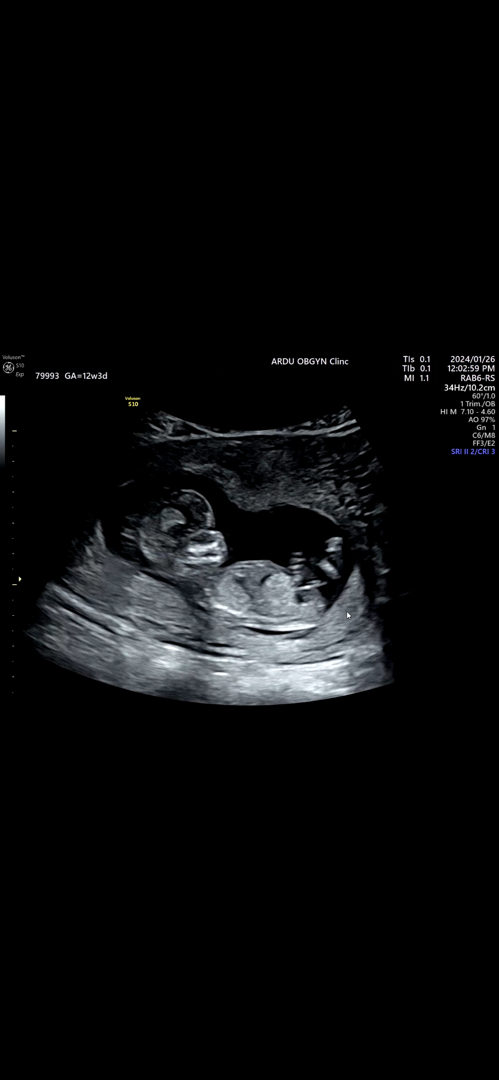

12주 5일 각도법 봐주세요!

각도법으로 봤을때 어때보이시나유..?

아들같네요